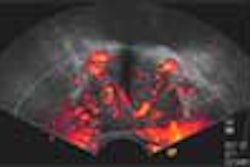

![]() |

| Infección cerebral por criptococos en el VIH. Imágenes cortesía del Dr. Peter Corr. |